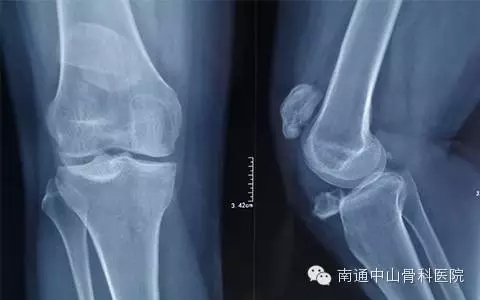

家住南通崇川区的张女士,1月11日来南通中山骨科医院就诊。原来14年前,张女士发生过一次意外车祸,导致其“右侧髌骨骨折”,活动受限,无法行走。其家人便带她到如皋的一家私人诊所诊治,二个月后,复查X线显示“右膝髌骨分离不愈合”,稍疼,但是可以行走,就未进行下一步治疗。

为了帮张女士及早解除痛苦,医务人员为她安排好一系列的检查,以便尽早治疗。根据患者的病史、体征及影像学检查,医生诊断张女士为:1、右髌骨陈旧性骨折骨不连2、右膝关节退变。综合多方讨论,医生决定为张女士行右髌骨骨折切开复位内固定术,以解决她现在的痛苦。

术前照片

1月14日上午8点30分,在腰硬联合麻醉下,由我院骨科李龙付主任亲自操刀,为患者行右髌骨骨折切开复位内固定术。患者为陈旧性骨折,骨折端移位接近10厘米,且断端硬化、缺血;连接骨折两端的韧带组织也已明显挛缩,手术相当麻烦。但李主任对手术早已胸有成竹,他先是将骨折的硬化骨咬除后复位,在髌骨周围用钢丝捆扎后初步固定,再用两枚空心钉固定骨折,并从空心钉中穿入钢缆进一步加强。这样的固定相当牢固,保证了患者术后能进行早期功能锻炼。同时李主任还将患者的韧带进行了松解,术中患者的膝关节的屈曲角度已达到了90度以上。手术进行的非常顺利。